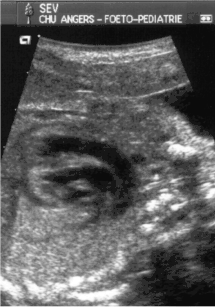

- le signe d'appel habituel est la perte du croisement des gros vaisseaux. Normalement, l'aorte et le tronc pulmonaire se croisent peu après leur sortie du cœur. Il est donc impossible de dérouler les deux vaisseaux sur un même plan de coupe. Quand l'aorte est vue longitudinalement, le tronc pulmonaire n'apparaît qu'en section transversale ("aorte en long, tronc pulmonaire en rond") et vice-versa. Dans la D-TGV simple, la plus fréquente, les vaisseaux ont un trajet parallèle et peuvent donc être visualisés longitudinalement simultanément.

- la confirmation est obtenue par l'analyse des gros vaisseaux et de leurs connexions aux ventricules. L'aorte est caractérisée par le fait qu'elle décrit une crosse, donne naissance aux vaisseaux à destinée céphalique et est le vaisseau qui monte le plus haut dans le thorax. Le tronc pulmonaire est caractérisé par sa bifurcation précoce en deux branches, les artères pulmonaires droite et gauche. Sur un cœur par ailleurs normal, le ventricule droit est situé en avant et à droite du ventricule gauche, le tronc pulmonaire est donc le vaisseau le plus antérieur. La TGV se caractérise par la position antérieure du vaisseau qui décrit la crosse et donne les vaisseaux céphaliques : l'aorte.

- La coupe parasternale gauche grand axe : elle montre que le vaisseau issu du ventricule gauche (le plus postérieur) se dirige anormalement vers l'arrière et se bifurque précocement. C'est donc le tronc pulmonaire et non l'aorte comme normalement.

- Les coupes sous costales qui montrent bien le trajet parallèle des gros vaisseaux et leur inversion. Cet examen permettra d'éliminer en particulier un retour veineux pulmonaire anormal total bloqué qui aurait pu rendre compte de l’hypervascularisation pulmonaire sur la radiographie des poumons.